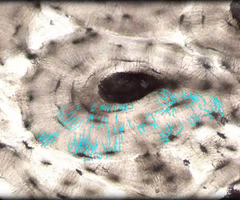

term image

simple squamous epithelia- single layer of flattened cells